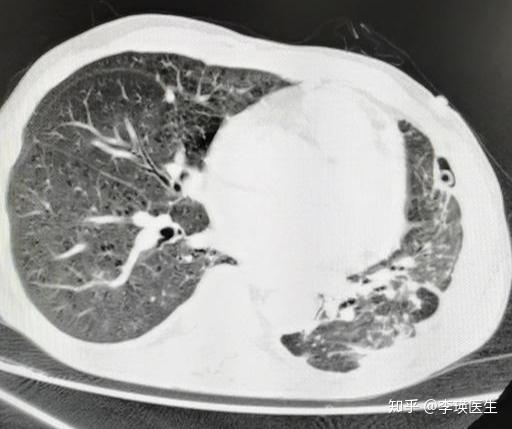

真菌性肺炎 68岁男性 肿瘤化疗期间 咳嗽发热, 经皮穿刺证实曲菌感染.